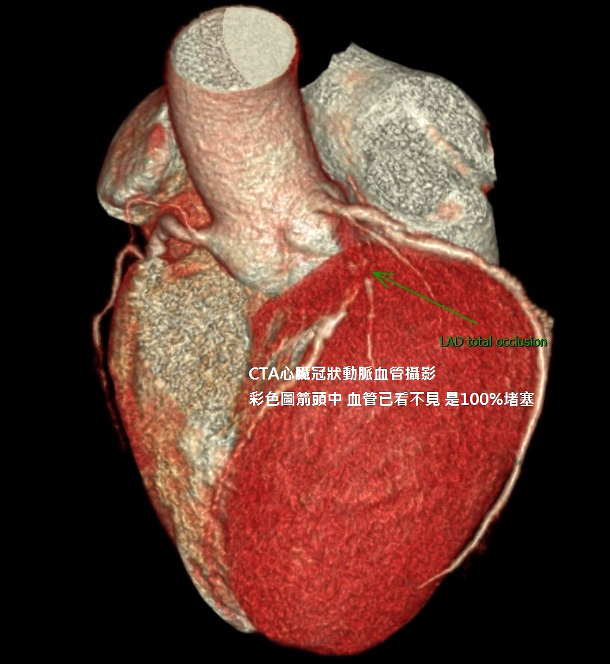

「朋友夫妻年過半百後愛上健走爬山,老婆常會氣喘吁吁,先生則是老神在在,同好都覺先生身體比老婆好,直到有天爬山途中先生偶感心會痛,返家後時好時壞,拖了幾天夫妻倆同時做進一步檢查,才發現代誌大條,先生有一條冠狀動脈狹窄幾近全塞…,而老婆心血管反而比先生還健康。」

我們身體的動靜脈及微血管連接起來長達十五萬公里,可繞地球兩圈,最重要的冠狀動脈直徑只有0.3~0.4公分,大約原子筆芯粗細,如果要了解自己整體心臟功能,錢副說較高階且精密的檢查,例如心臟冠狀動脈血管攝影(CTA,利用非侵入式電腦斷層掃描後,影像結果結合3D立體圖技術,可清楚分析心臟冠狀動脈鈣化及堵塞的程度)、心導管檢查(侵入性打顯影劑進行冠狀動脈攝影),而大家比較熟悉的心電圖、運動心電圖都屬間接及較初步的檢查方式。

↑心臟冠狀動脈血管攝影(CTA)心臟3D影像造影。